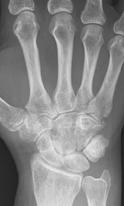

RA – Damaged fingers and wrist RA – Fused wrist bones

https://commons.wikimedia.org/wiki/File:Rheumatoid_arthritis_with_carpal_ankylosis_2017.jpg

Description    English:

X-ray of the wrist of a 66 year old

woman with rheumatoid arthritis, showing ankylosing fusion of the carpal bones. Previous X-ray showed unaffected carpal bones - see File:Rheumatoid arthritis with unaffected carpal bones 2009.jpg.

Date               19 January 2017

Source            Own work

Author            Mikael Häggström